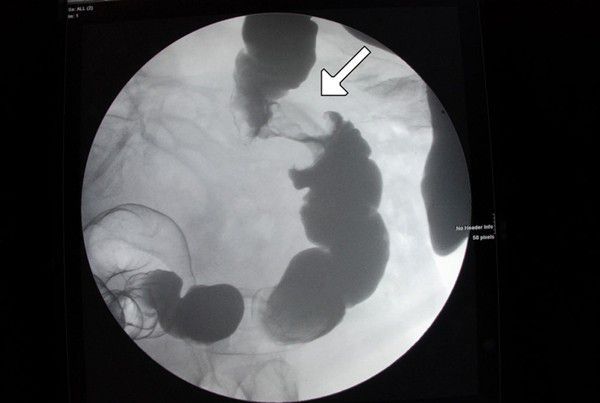

Apple core sign is a characteristic finding in stenosing annular colorectal carcinoma. The typical appearance is attributed to constriction of lumen. It is also known as ‘napkin sign’. In addition to colorectal carcinoma, apple core sign may also be present in case of Crohn’s disease, ulcerative colitis, ischemic colitis, lymphoma, tuberculosis, and villous adenoma. Reference: https://radiopaedia.org/articles/apple-core-sign-colon-1 Image via: https://www.researchgate.net/publication/38094336_Apple-core_lesion_of_the_colon_A_case_report/figures?lo=1&utm_source=google&utm_medium=organic